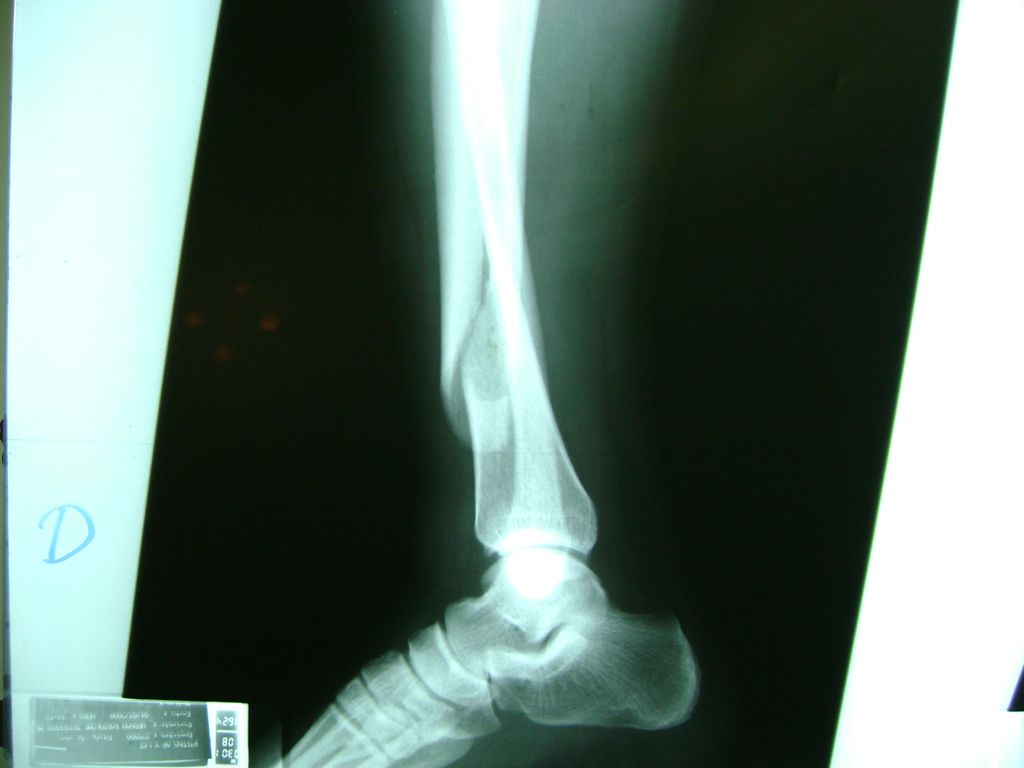

Cirugías de Calcaneo - Perone y Tibia

Aunque cada uno de estos huesos puede fracturarse por separado, normalmente la rotura es una lesión que se produce de forma conjunta

La mayor parte de las roturas implican a la parte proximal del hueso (parte del hueso próximo a la rodilla) o a la parte distal (parte del hueso cerca del tobillo).

Debido a la fina cobertura de piel que recubre la tibia y el peroné, las fracturas generalmente son abiertas, es decir, el hueso roto rasga la piel, atravesándola. Las fracturas de tibia y peroné generalmente se producen por un fuerte impacto o torsión.